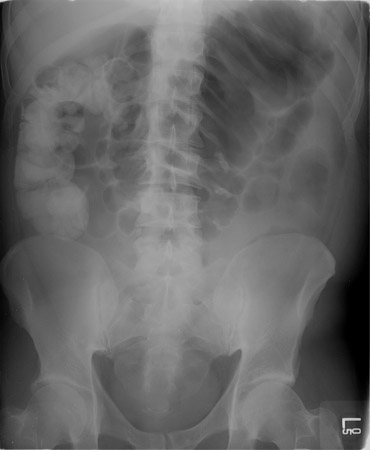

Colite tóxica e megacólon tóxico

Radiografia abdominal demonstrando dilatação colônica

University of Chicago Medical Center; usado com permissão